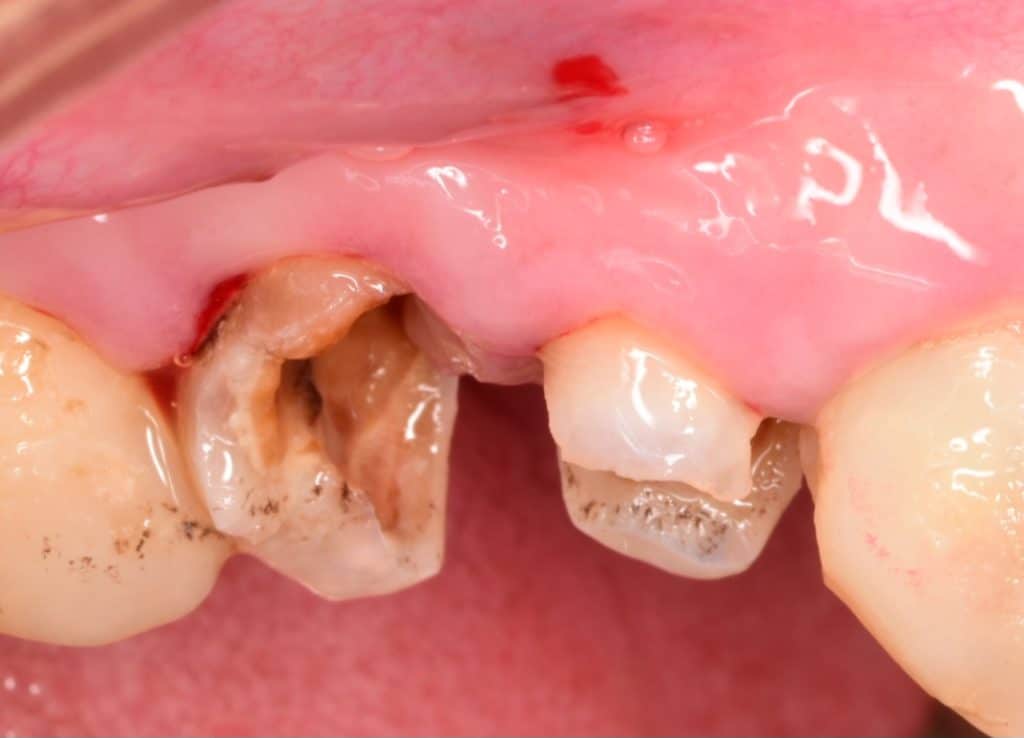

Buccal view showing the extension of the caries

Buccal view showing the final cavity